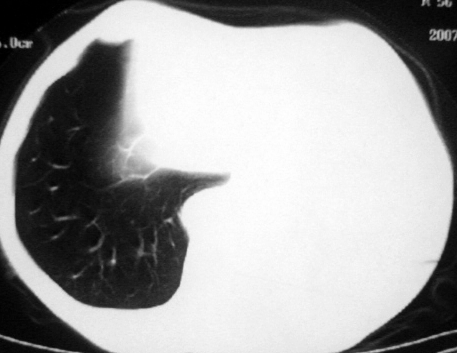

男,54岁,咳嗽,气喘半年,胸痛一月.

血性胸水

左侧中心型肺癌并阻塞性肺炎、肺膨胀不全,左胸腔、心包积液

左肺下叶中心型肺癌并阻塞性肺炎左肺膨胀不全伴左侧胸腔积液